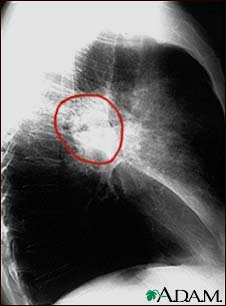

Lung cancer, lateral chest X-ray

A lateral view of a CXR in a patient with central cancer of the lung.